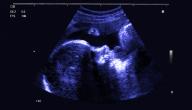

التغيرات في الشهر الخامس من الحمل

تحدث مجموعة من التغييرات في جسم الجنين أثناء مرحلة الحمل، وتبدأ منذ بداية هذه المرحلة حتى اكتمال نموه داخل رحم أمه، وفي كل أسبوع من الحمل تطرأ عليه تغييرات جديدة في الشكل والحجم والتكوين، وفي ما يأتي أبرز التغيّرات الحاصلة للجنين خلال الشهر الخامس من الحمل:

• الأسبوع 18: إذ يزن الجنين حوالي 191 غرامًا، في حين يصل طوله من الرأس حتى الأرداف إلى حوالي 14 سنتيمترًا، ويكون حجمه مثل حجم حبة الفليفلة، بالإضافة إلى ما يأتي:[٢]

• الأسبوع 19: إذ يزن الجنين حوالي 227 غرامًا، في حين يصل طوله من الرأس حتى الأرداف إلى حوالي 15 سنتيمترًا، ويكون حجمه كحجم حبة الطماطم، بالإضافة إلى ما يأتي:[٣]

• الأسبوع 20: تُؤخذ قياسات جسم الجنين مع بدء هذا الأسبوع بنحوٍ مختلفٍ؛ إذ يُقاس طوله ابتداءً من رأسه حتى أصابع قدميه عوضًا عن قياس الطول التاجي المقعدي، ويبلغ طوله حوالي 25 سنتيمترًا، ويكون حجمه كحجم حبة الموز، ومن أبرز التغييرات الحاصلة للجنين خلال هذا الأسبوع ما يأتي:[٥]

• الأسبوع 21: يزن الجنين حوالي 340 غرامًا، في حين يصل طوله إلى حوالي 27 سنتيمترًا كطول حبة الجزر، بالإضافة إلى ما يأتي:[٦]

• الأسبوع 22: إذ يزن الجنين حوالي 450 غرامًا، بينما يصل طوله إلى حوالي 28 سنتيمترًا وحجمه كحجم حبة القرع، بالإضافة إلى ما يأتي:[٧]